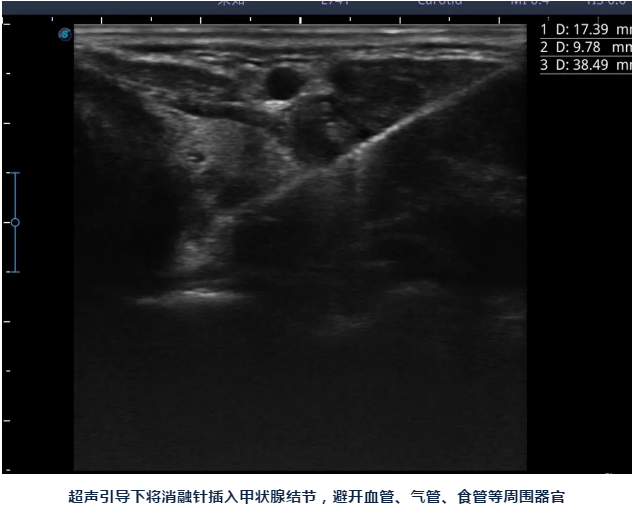

陈主任说:甲状腺结节消融做完后脖子上只有一个针眼,术后也不影响活动、进食,同时手术是在超声引导下进行,只消融结节,能尽最大限度保护正常甲状腺组织,也可以清楚避开血管、气管、食管、神经等周边组织器官,术后出现声音嘶哑、出血、甲减的几率要小很多。